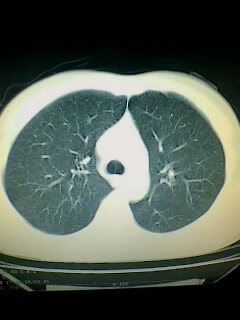

标题: CT28315:咳嗽咳痰咯血半月并胸痛 [打印本页]

标题: CT28315:咳嗽咳痰咯血半月并胸痛

1、纵膈窗效果不好,初步考虑左肺下叶感染性病灶,建议正规抗炎治疗后复查   2、右肺下叶陈旧性病灶伴局部胸膜增厚。

考虑左肺下叶周围型肺癌.图象欠清,请问病人贵更?

考虑左肺下叶周围型肺癌.

图像资料欠清,建议强化,考虑周围型肺癌。

左下肺肿块影,深分叶,考虑肺癌。

左下肺球形病灶,考虑:1:球形肺炎;2:周围型肺癌不除外,建议治疗后复查

不排除左肺下叶周围型肺癌可能!建议穿刺活检!

考虑左肺下叶周围型肺癌。

考虑左肺下叶周围型肺癌并阻塞性肺炎。

考虑左肺下叶周围型肺癌